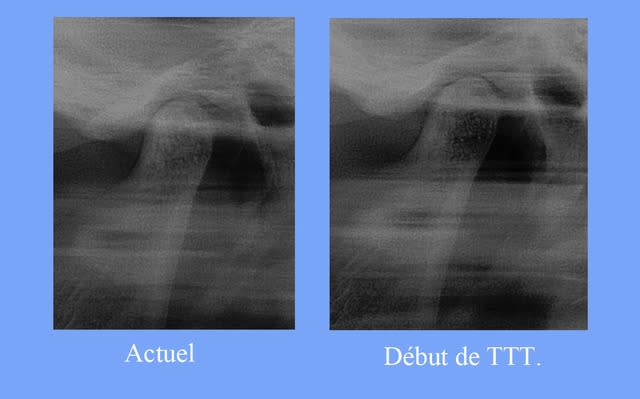

Quand aux radios, on ne voit effectivement aucune différence entre avant et après. Si jeff n'avait pas fait l'effort de rechercher les premières, on aurait tous été piégés.

En fait en observant le montage des 2 radios (merci Jeff pour l'avoir montré), je ne vois pas vraiment de différence au niveau de la position des condyles, par contre avant la radio est prise avec des dents en inoclusion et après en occlusion, on peut donc imaginer que si la radio avait été prise au départ en occlusion on aurait pu voir des condyles remonter et/ou reculer et comprimer alors ménisque et zone bilaminaire . Attention on est au conditionnel, est donc la radio ne prouve rien, et ça je pense que tout les passager du A380 l'ont vu.

la dérotation des 6 a entrainé

une surélévation qui s’objective par une innocclusion Post.

Ce qui entraine un soulagement de la pression de la tète du condyle G. dans la glène et le soulagement de la patiente

Des modification de surface de la tète de l’ATM. gauche

position plus Ant.

Un début de cicatrisation osseuse, la dentelure de la partie Ant. de la tète condylienne est remplacée par une ligne callipyge

le mesnisque G. est toujours en position Ant., dans quel état, je ne sais pas, seul un IRM. pourrait me le dire. Si je n’en fais pas actuellement, c’est pour éviter trop de rayons à ma patiente